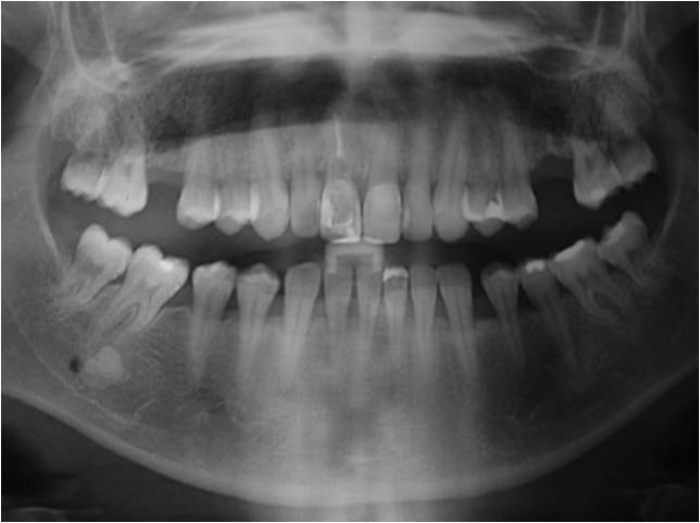

Raio X inicial